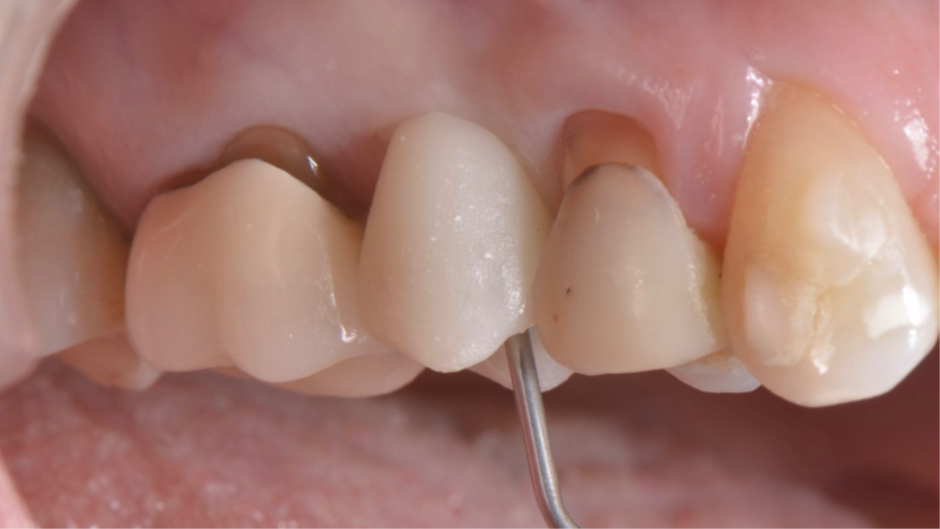

Após a finalização, os dentes adjacentes foram preparados e também receberam coroas provisórias, e a coroa sobre implante provisória foi parafusada no pilar Ideale (Figura 15) usando uma combinação de pressão digital e apertamento do paciente em um rolo de algodão. A isquemia dos tecidos moles peri-implantares pode ser observada, e geralmente desaparece em até 20 minutos. A coroa sobre implante provisória deve ser deixada por um período mínimo de um mês para permitir o adequado condicionamento dos tecidos moles peri-implantares 11,12 (Figura 16). Foi necessário um exame periódico para garantir que a higiene bucal adequada fosse mantida. Após dois meses, quando a mucosa condicionada se estabilizou 13, foi realizado um escaneamento intraoral (Figura 17) para a confecção das coroas definitivas (Figura 18). As coroas definitivas foram fabricadas fresadas em zircônia pura, e após instaladas (Figura 19), o resultado estético e funcional ficou muito favorável (Figura 20).

Figura 15 – Coroa sobre implante provisório parafusada no pilar Ideale.

Figura 16 – Condicionamento dos tecidos moles peri-implantares após um mês.